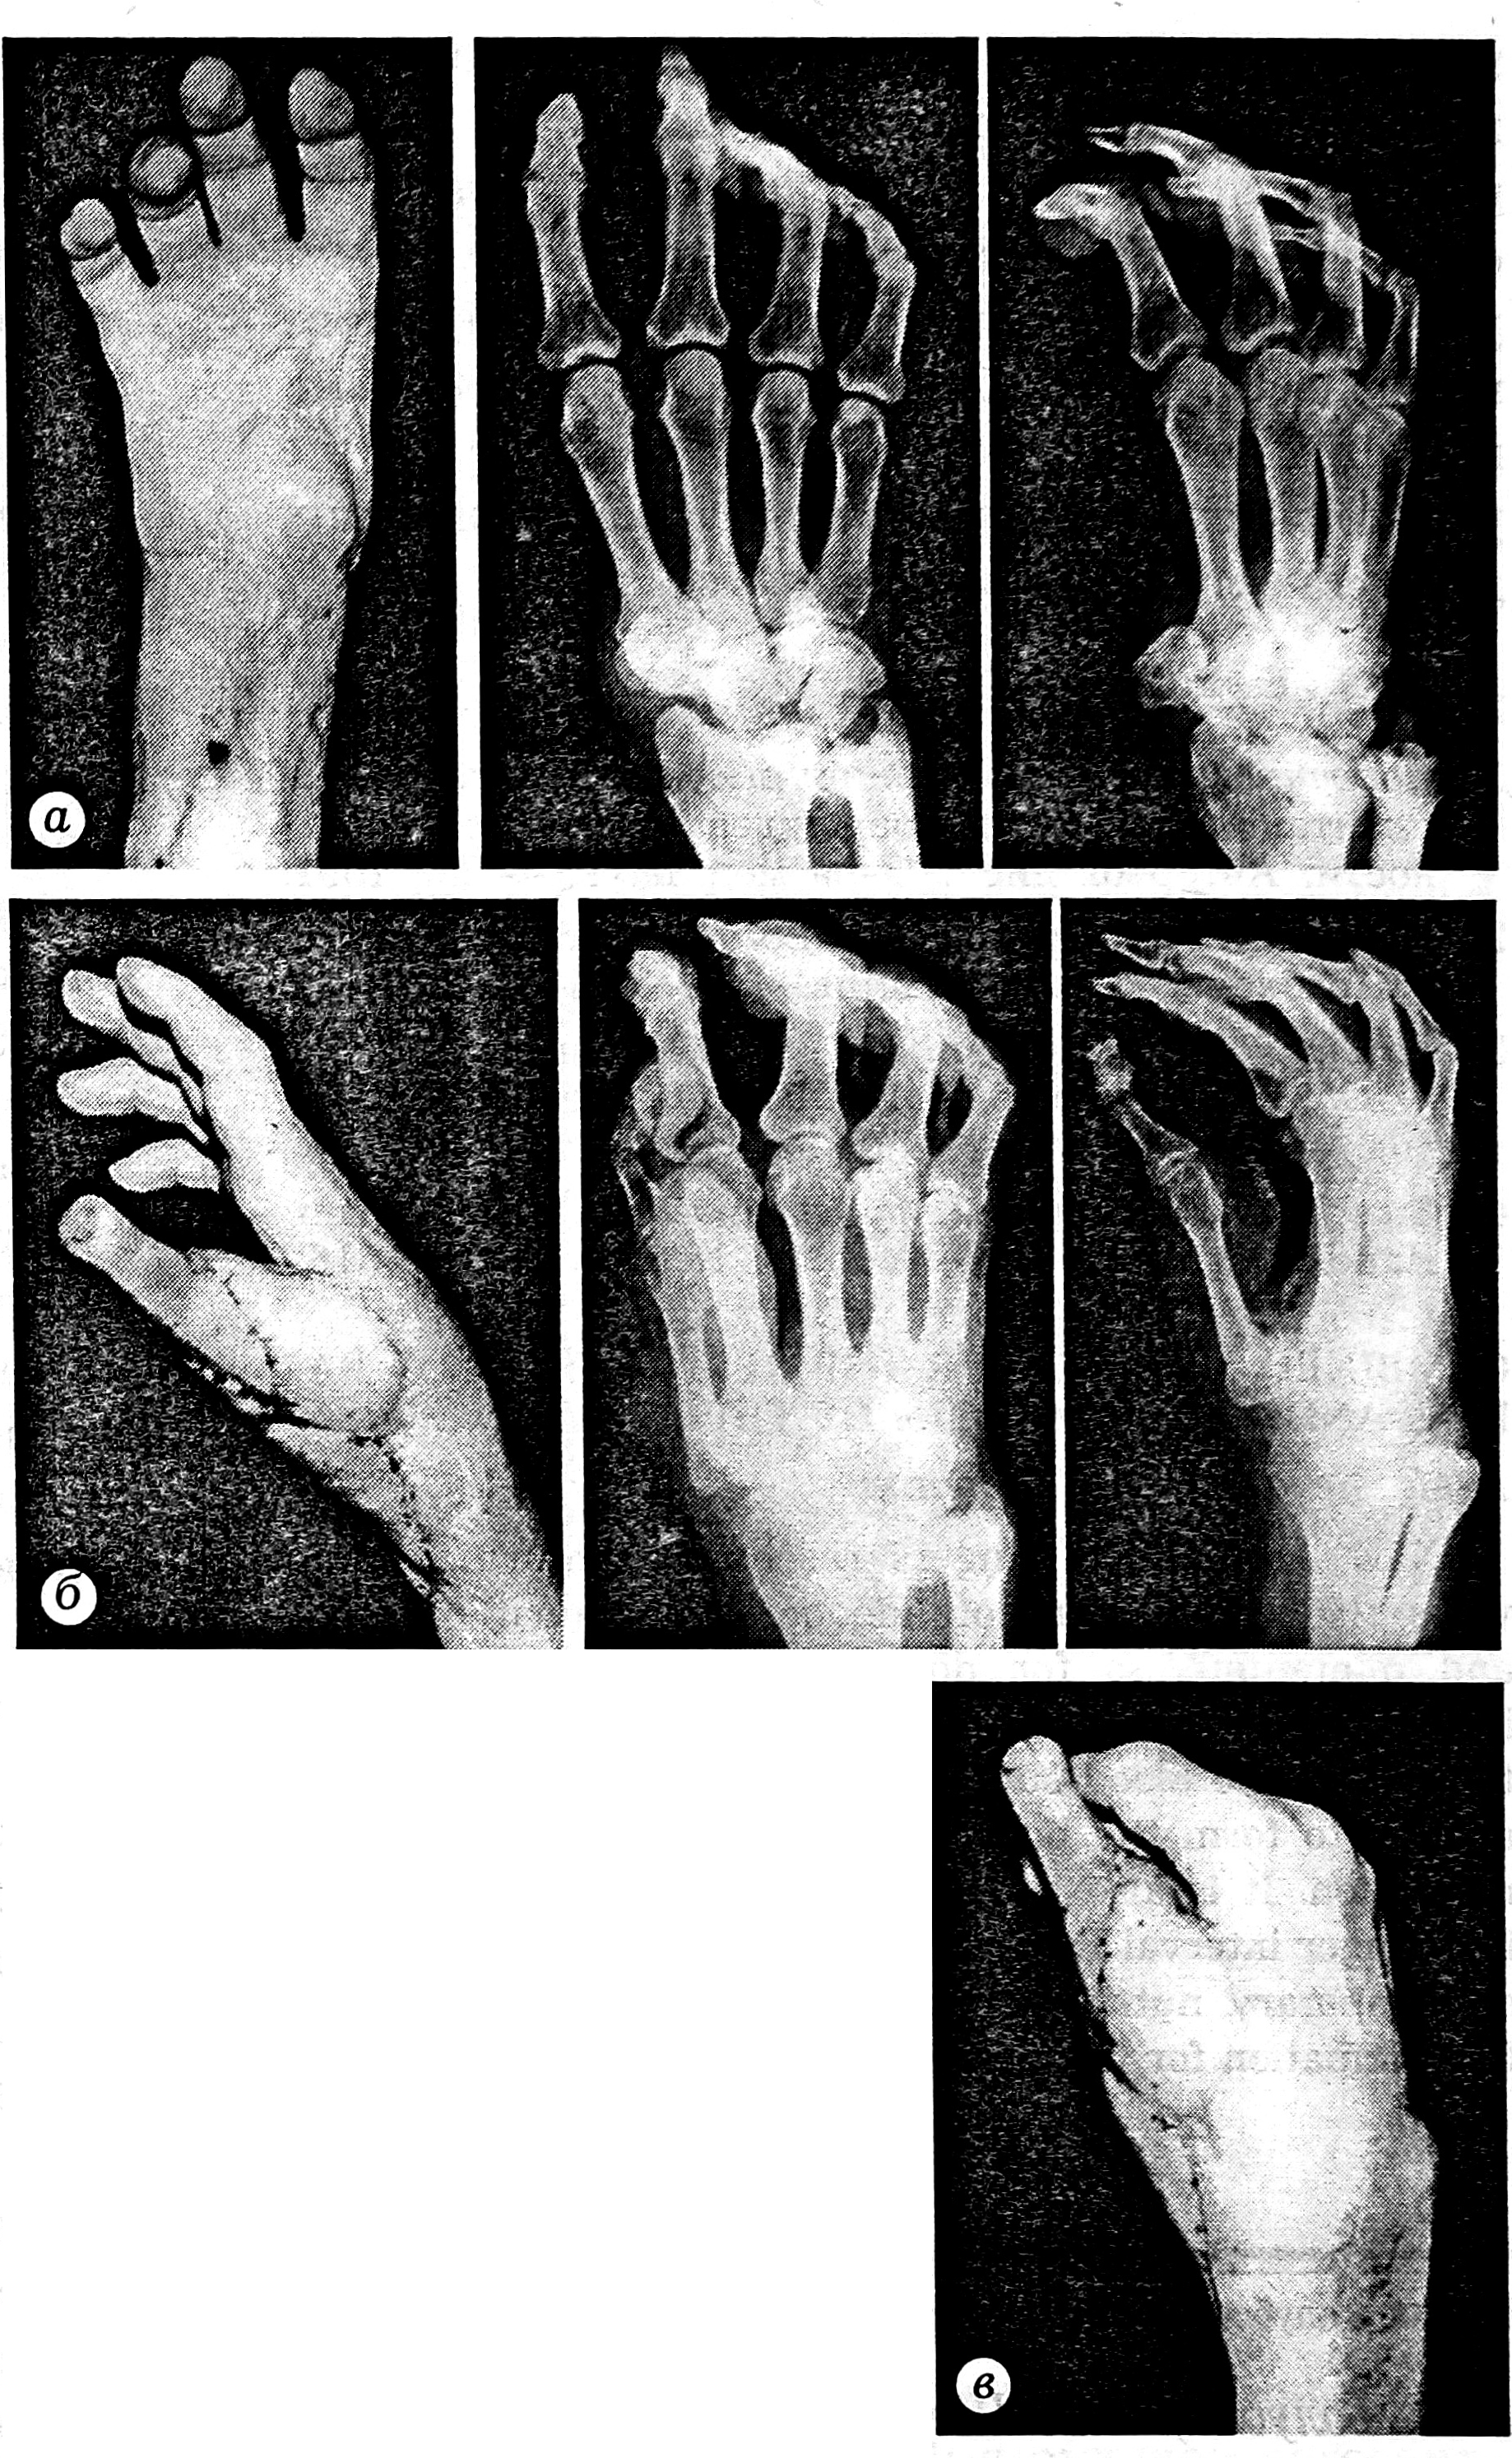

Рис. 3. Больной С.

а — внешний вид и рентгенограммы кисти до операции; б — внешний вид и рентгенограммы кисти, в — функциональный результат через 1 год после операции.

Таким образом, предложенный нами подход позволил восстановить двусторонний схват даже при тяжелых дефектах и деформациях кисти.Пациент осмотрен 21.02.94. Восстановленный палец находится в положении пассивного противопоставления остальным. Возможен двусторонний схват кистью за счет движений II-V пальцев в пястно-фаланговых суставах и фиксации восстановленного пальца в положении умеренного приведения (рис. 3, б, в). В зоне иннервации локтевого нерва отмечается восстановление болевой чувствительности. На рентгенограммах кисти отчетливо определяется консолидация фрагмента плюсневой кости с костями запястья. Пациент активно пользуется кистью в повседневной жизни.